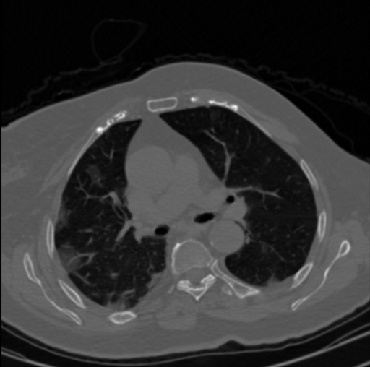

Early and reliable COVID-19 diagnosis based on chest 3-D CT scans can assist medical specialists in vital circumstances. Deep learning methodologies constitute a main approach for chest CT scan analysis and disease prediction. However, large annotated databases are necessary for developing deep learning models that are able to provide COVID-19 diagnosis across various medical environments in different countries. Due to privacy issues, publicly available COVID-19 CT datasets are highly difficult to obtain, which hinders the research and development of AI-enabled diagnosis methods of COVID-19 based on CT scans. In this paper we present the COV19-CT-DB database which is annotated for COVID-19, consisting of about 5,000 3-D CT scans, We have split the database in training, validation and test datasets. The former two datasets can be used for training and validation of machine learning models, while the latter will be used for evaluation of the developed models. We also present a deep learning approach, based on a CNN-RNN network and report its performance on the COVID19-CT-DB database.